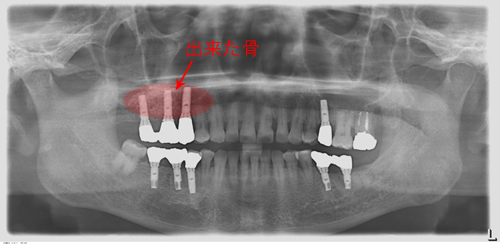

奥歯は骨が少なく、骨をつくり、インプラント治療をしました。赤く囲ったところが出来た骨です。